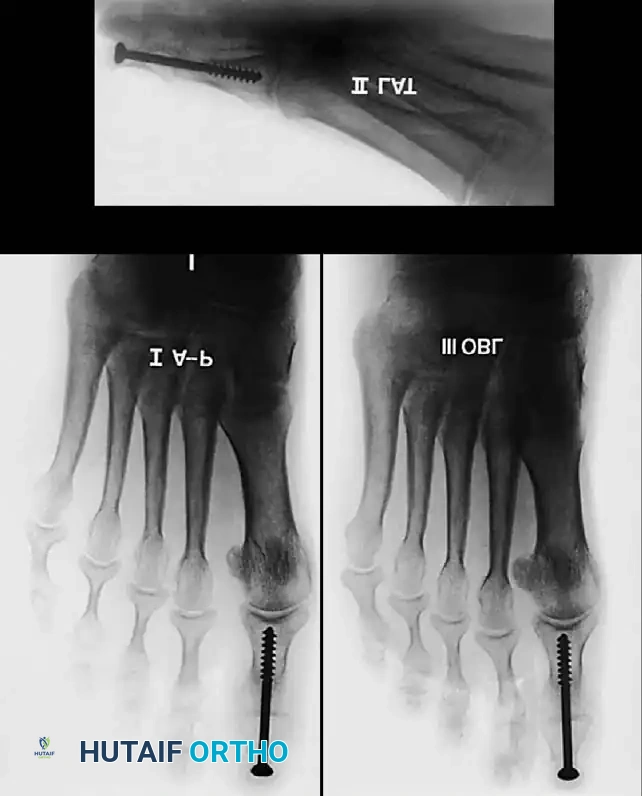

Keller Resection Arthroplasty The Keller procedure combines resection hemiarthroplasty of the fi rst metatarsophalangeal joint with removal of the medial eminence of the fi rst metatarsal (Fig. 78-28). Although removing the base of the proximal phalanx decompresses the joint and mobilizes the hallux, allowing marked correction of valgus, the varus of the fi rst metatarsal is not corrected, and maintaining correction of the valgus of the hallux is diffi cult. Other complications of the Keller procedure have been emphasized in the literature to such an extent (with neither the incidence nor the severity of such complications clearly documented) that the indications for this procedure have been limited severely. In our experience, however, complications are uncommon if patients are selected carefully. Modifi cations in the original technique also have allowed expansion of the indications for the Keller bunionectomy. Candidates for the Keller procedure are patients older than 50 years with moderate-to-severe hallux valgus (30 to 45 degrees); intermetatarsal angles of 13 degrees or less, indicating mild-to-moderate metatarsus primus varus; and pain over the medial eminence with any shoe worn, so the variety of shoes the patient can wear is severely limited. An incongruous fi rst metatarsophalangeal joint caused by

Fig. 78-26 Modifi ed McBride bunionectomy (DuVries; Mann). A, Medial capsule of second metatarsophalangeal joint is sutured to lateral capsule of fi rst metatarsophalangeal joint with interposition of released adductor hallucis. B, Medial capsular resection. C, Confi guration after capsular resection. D, After capsular imbrication, hallux should rest in neutral position or not exceed 5 degrees of varus. E, Postoperative dressing technique (Mann). ( E after Beverly Kessler; courtesy of LTI Medica and The Upjohn Company.) lateral subluxation of the phalanx on the metatarsal head, severe lateral displacement of the sesamoids, and any evidence of degenerative cartilage changes in the joint all are radiographic indications for the Keller procedure. Two modifi cations in technique can expand these indications, however, to include patients with more severe deformities (Fig. 78-29) (but not to include younger patients): fi bular sesamoidectomy and lateral displacement of the fi rst metatarsal. Using these modifi cations, Donley et al. obtained an average 18-degree correction of the metatarsophalangeal angle and an average 6-degree correction of the intermetatarsal angle in 38 patients (50 feet);

Fig. 78-28 A, Anteroposterior radiograph of right foot of 65-year-old patient shows mild-to-moderate deformity and mild degenerative changes at fi rst metatarsophalangeal joint; patient had intraarticular and periarticular symptoms. B, Twelve years after Keller procedure with excision of fi bular sesamoid; note correction of fi rst metatarsal varus and maintenance of enough joint space to allow functional range of motion.

95% of patients were satisfi ed with their results. Patients with 50 degrees or more of valgus of the hallux (18 to 20 degrees of varus of the fi rst metatarsal), complete lateral dislocation of the sesamoids, marked degenerative changes, and severe pronation of the hallux may benefi t functionally and cosmetically from alterations of the standard technique.

D

Fig. 78-29 Severe hallux valgus with bursa formation in 70-year-old woman. A and B, Anteroposterior and lateral clinical photographs of patient’s right foot. C, Correction of deformity by modifi ed Keller procedure. D, Preoperative and postoperative weight bearing radiographs of same patient.